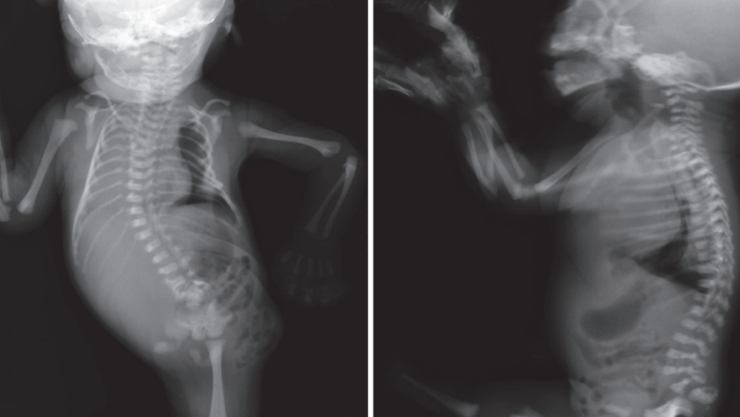

Salud.- La sirenomelia, o mejor conocida como el síndrome de la sirena, es un raro padecimiento que causa una malformación vascular severa, se caracteriza por la fusión de las extremidades inferiores del cuerpo humano, uniendo la piel y la estructura ósea asimilando a la cola de una sirena.

Además, esta enfermedad afecta directamente el desarrollo de algunos órganos vitales del cuerpo humano, tal como la falta de riñones y pulmones, ano imperforado y malformaciones en la columna, el corazón y el sistema digestivo.